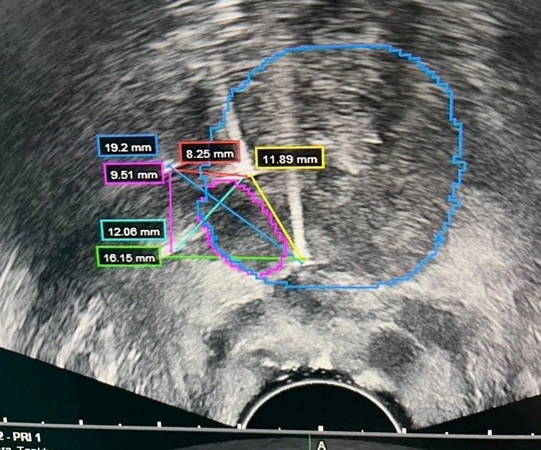

ร.พ.สมเด็จพระนางเจ้าสิริกิติ์ กรมแพทย์ทหารเริอ อ.สัตหีบ จ.ชลบุรี ได้ดำเนินการรักษาผู้ป่วยด้วยเทคนิค IRE (Irreversible Electroporation) Focal Prostate Therapy เป็นรายแรก สำเร็จลุล่วง เมื่อวันที่ 5 เม.ย.69 นับเป็นอีกหนึ่งความก้าวหน้าทางการแพทย์ที่มุ่งเน้นการรักษาแบบจำเพาะจุด (Focal Therapy) เพื่อลดผลกระทบต่อเนื้อเยื่อข้างเคียง และคงคุณภาพชีวิตของผู้ป่วยให้ได้มากที่สุด

IRE เป็นนวัตกรรมการรักษาที่ใช้กระแสไฟฟ้าความเข้มสูงในการทำลายเซลล์มะเร็งเฉพาะบริเวณเป้าหมาย โดยไม่ก่อให้เกิดความร้อนสูง จึงช่วยลดความเสียหายต่อโครงสร้างสำคัญ เช่น เส้นประสาทและหลอดเลือดบริเวณรอบข้าง ส่งผลให้ลดภาวะแทรกซ้อน เช่น ภาวะกลั้นปัสสาวะไม่ได้